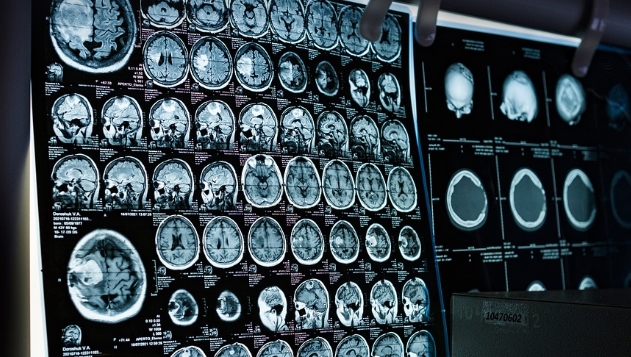

CT·Î Æó¾Ï Á¶±â ¹ß°ß, »ýÁ¸À² Çâ»ó

Á¶±â ¹ß°ß»ç·Ê 81%°¡ 20³â ÈÄ¿¡µµ »ýÁ¸

Èí¿¬ÀÚ¿Í Èí¿¬ÇÏ´Ù ±Ý¿¬ ÁßÀÎ »ç¶÷µéÀÇ °æ¿ì ¸Å³â ÈäºÎ CT ½ºÄµÀ» ¹Þ¾Æ Æó¾ÏÀ» Á¶±â¿¡ ¹ß°ßÇÏ¸é »ýÁ¸À²ÀÌ ±ØÀûÀ¸·Î Çâ»óµÈ´Ù´Â »õ·Î¿î ¿¬±¸ °á°ú°¡ ³ª¿Ô´Ù.

¸¹Àº »ç¶÷µéÀº Æó¾ÏÀÌ Ä¡¸íÀûÀ̶ó°í ¹Ï°í ÀÖÀ¸³ª »õ·Î¿î º¸°í¿¡ µû¸£¸é CT °Ë»ç¸¦ ÅëÇØ Á¾¾çÀ» Á¶±â¿¡ ¹ß°ßÇÑ »ç¶÷ÀÇ 81%´Â 20³â ÈÄ¿¡µµ ¿©ÀüÈ÷ »ýÁ¸Çϰí ÀÖ´Ù´Â °ÍÀÌ´Ù.

ƯÈ÷ ¾ÏÀÌ Ãʱ⠴ܰ迡 ÀÖÀ» ¶§ ¾Ï Áø´ÜÀ» ¹Þ°Ô µÇ¸é 20³â »ýÁ¸À²ÀÌ 95%±îÁö Áõ°¡Çß´Ù.